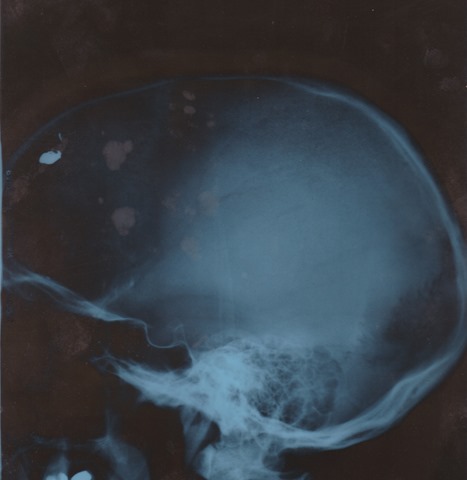

The x-rays of the bullet lodged in the frontal lobe of my brain make the point; life happens to us whether we like it or not. So does death.  So do experiences whose realities are so ruthlessly sudden and savage that when (if) you come out the other side with something resembling your wits about you,  you’ll likely find yourself viewing things from a new perspective.  Kahrmann Head Xray 3

Now, needless to say, when I was held up in Brooklyn  in 1984 and shot in the head, things changed. Far, far more than even I realized at the time. The mind and body, it seems, have a way of digesting certain realities over time, particularly when trauma is involved. Were they to absorb so massive a reality in one fell swoop, I suspect some would implode. That would’ve been my fate.